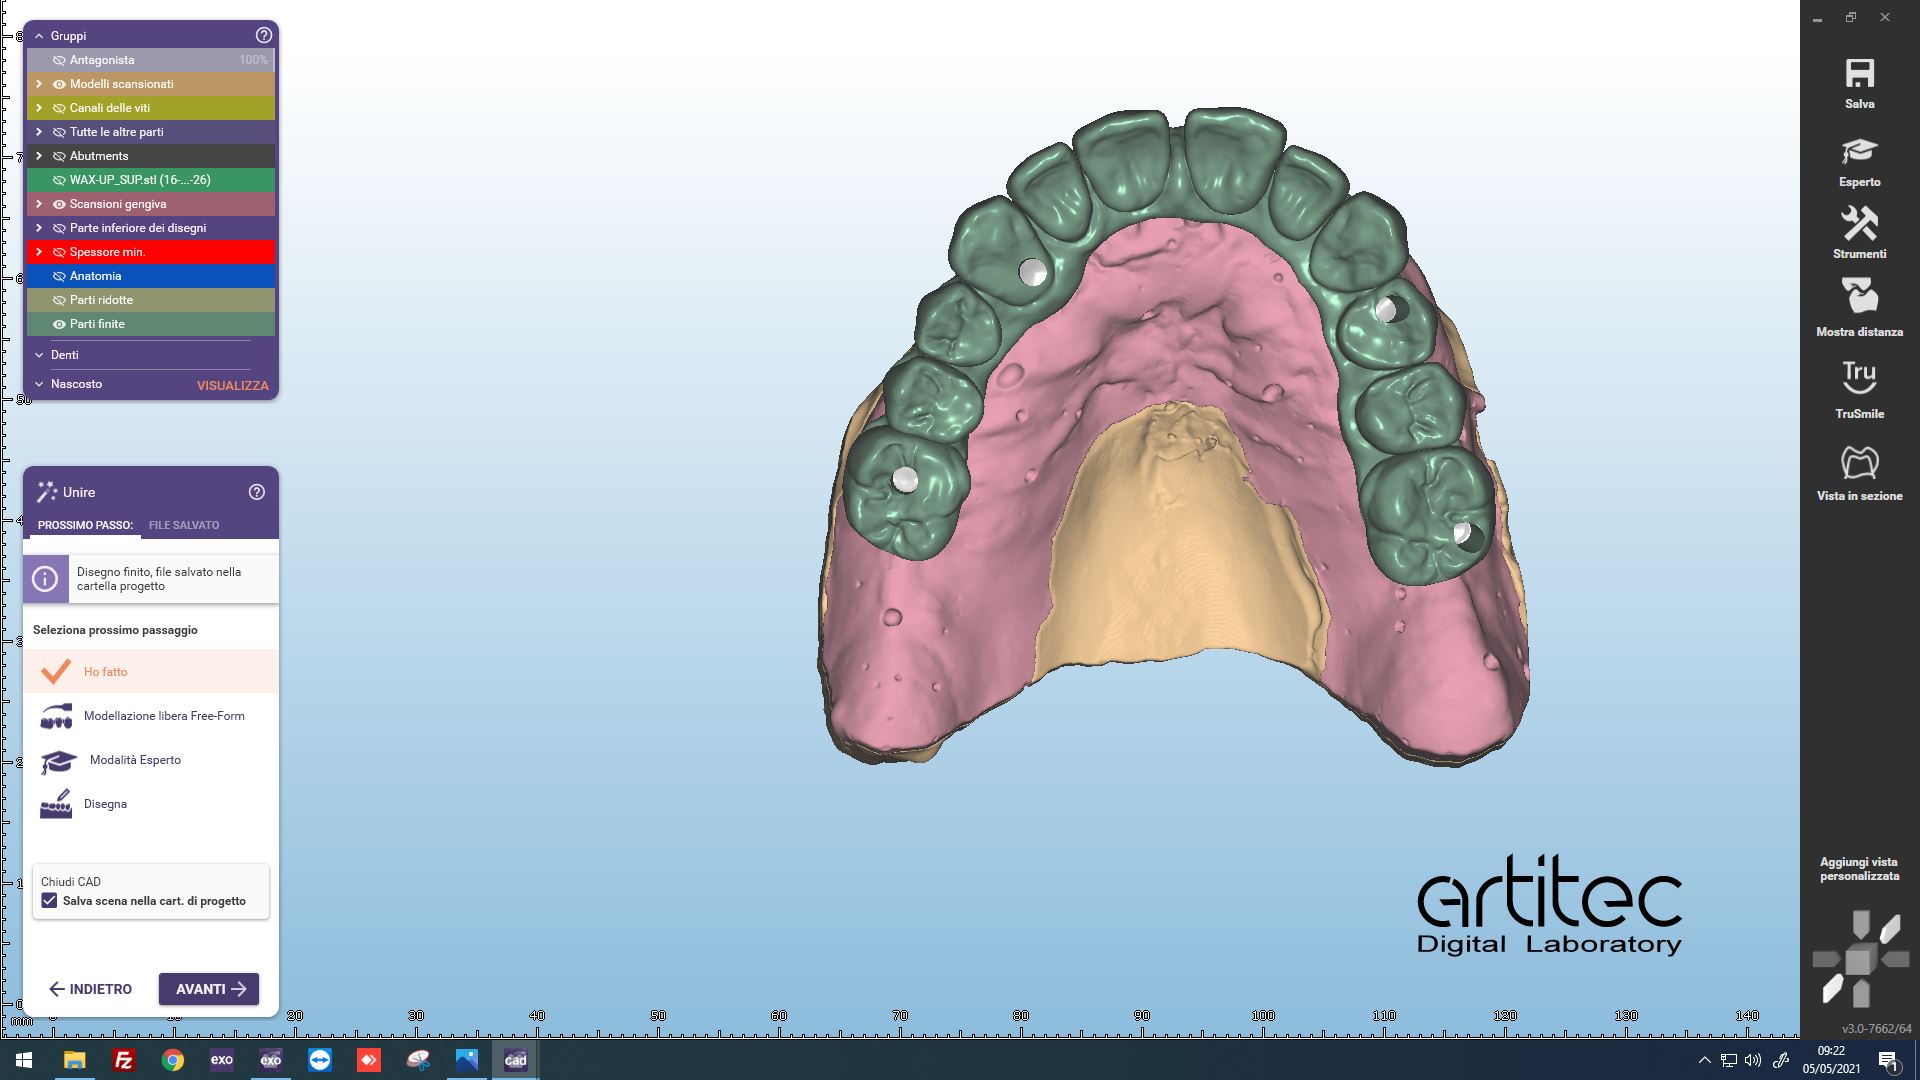

Fig. 9 Anatomie del progetto virtuale del defintivo

Fig. 10 Vista occlusale del progetto virtuale definitivo

Fig. 11 Vista laterale del progetto virtuale definitivo